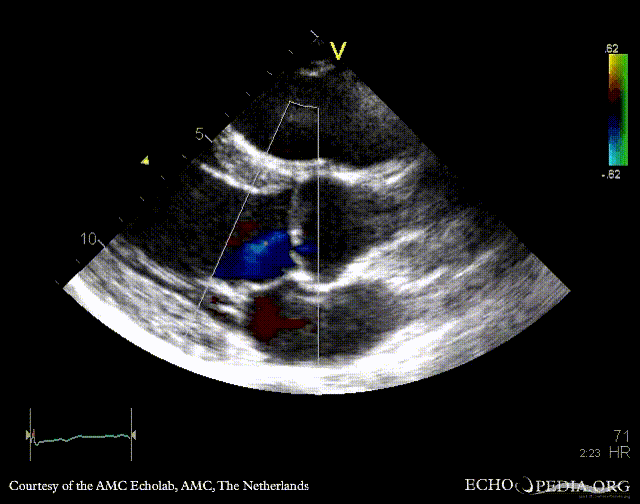

E00335.gif E00336.gif

PLAX: bicuspid aortic valve, doming of aortic valve PLAX: Color Doppler, mild aortic regurgitation